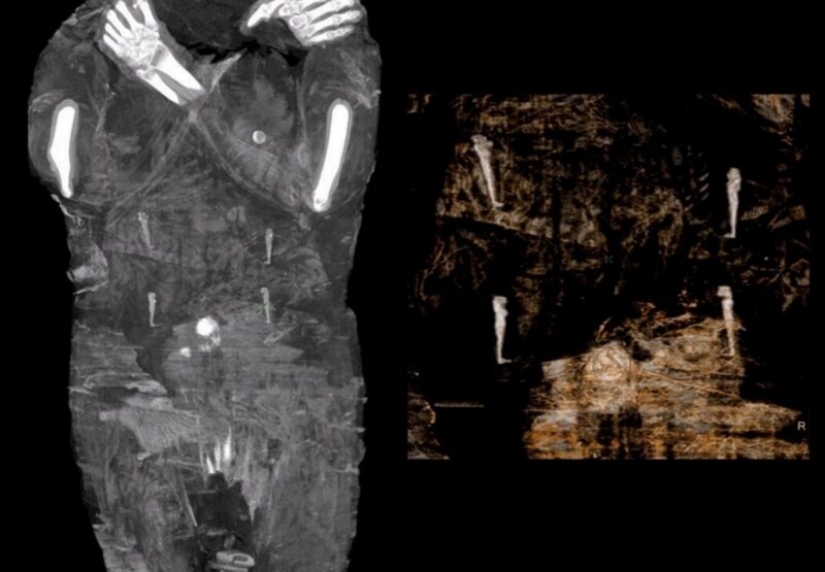

Para el nuevo estudio, los científicos decidieron escanear el cuerpo y se sorprendieron al encontrar que, de hecho, una mujer en el séptimo mes de embarazo está acostada en el ataúd.

Según los científicos, este es el único caso conocido de una momia egipcia embarazada bien conservada. Determinaron que la mujer tenía entre 20 y 30 años. Y el tamaño del cráneo fetal sugiere que estaba entre 26 y 28 semanas de embarazo.

Según el autor del estudio, el Dr. Wojciech, el niño fue dejado en el cuerpo de la madre porque aún no había nacido y no había recibido un nombre. Esto afecta directamente el hecho de que no sería capaz de ir en un viaje después de la vida, y por lo tanto los embalsamadores decidieron eliminar solo los órganos internos de la mujer.